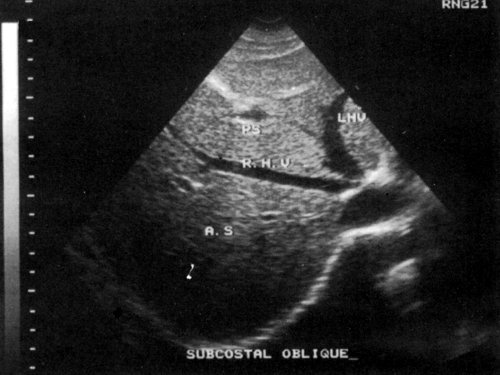

Помещаем датчик под правый нижний реберный край (рис. 3) и, легко нажимая на кожу, производим веерообразные движения сверху вниз и снаружи кнутри (рис. 4). Когда мы направляем датчик вверх, то видим печеночные вены (рис. 5) и изучаем сегментарное строение печени. Затем, направляя датчик немного вниз, можно увидеть вены воротной системы (рис. 6).

Рис. 5. УЗИ печеночных вен.а) Уровень расположения печеночных вен (схема).б) Нормальное изображение печеночных вен (эхограмма).

Рис. 6. Уровень бифуркации.а) Уровень бифуркации достигается при направлении датчика немного каудально (схема).б) Нормальное изображение воротных вен на уровне бифуркации (эхограмма).

Сегментарное строение печени

Сегментарное строение печени — важная часть ультразвукового исследования, поскольку информация о том, в каком сегменте органа располагается поражение имеет большое значение. Печень может быть разделена печеночными венами следующим образом: правая вена делит правую долю на два сегмента — задний и передний (рис. 10) и левая вена разделяет левую долю на латеральный и медиальный сегменты (рис. 11). Теперь, если мы проведем продольные плоскости через левую, среднюю и правую главные воротные вены (рис. 12), то печень будет разделена на восемь сегментов (рис. 13).

Рис. 10. Подреберный косой срез через правую долю печени позволяет увидеть передний и задний сегменты (эхограмма).

Рис. 11. Медиальный и латеральный сегменты левой доли печени (эхограмма).

Рис. 12. Продольные плоскости, проведенные через левую, среднюю и правую ветви воротной вены.

RHV — правая печеночная вена, MHV — средняя печеночная вена, LHV — левая печеночная вена, RPV — правая главная воротная вена, LPV — левая главная воротная вена.

Рис. 13. Печень разделена на восемь сегментов следующим образом: 1 — хвостатая доля, которая ограничена сзади нижней полой веной и спереди главной печеночной бороздой; 2 и 3 — левый латеральный сегмент; 4 — левый медиальный сегмент; 5 и 8 — правый передний сегмент; 6 и 7 — правый задний сегмент.